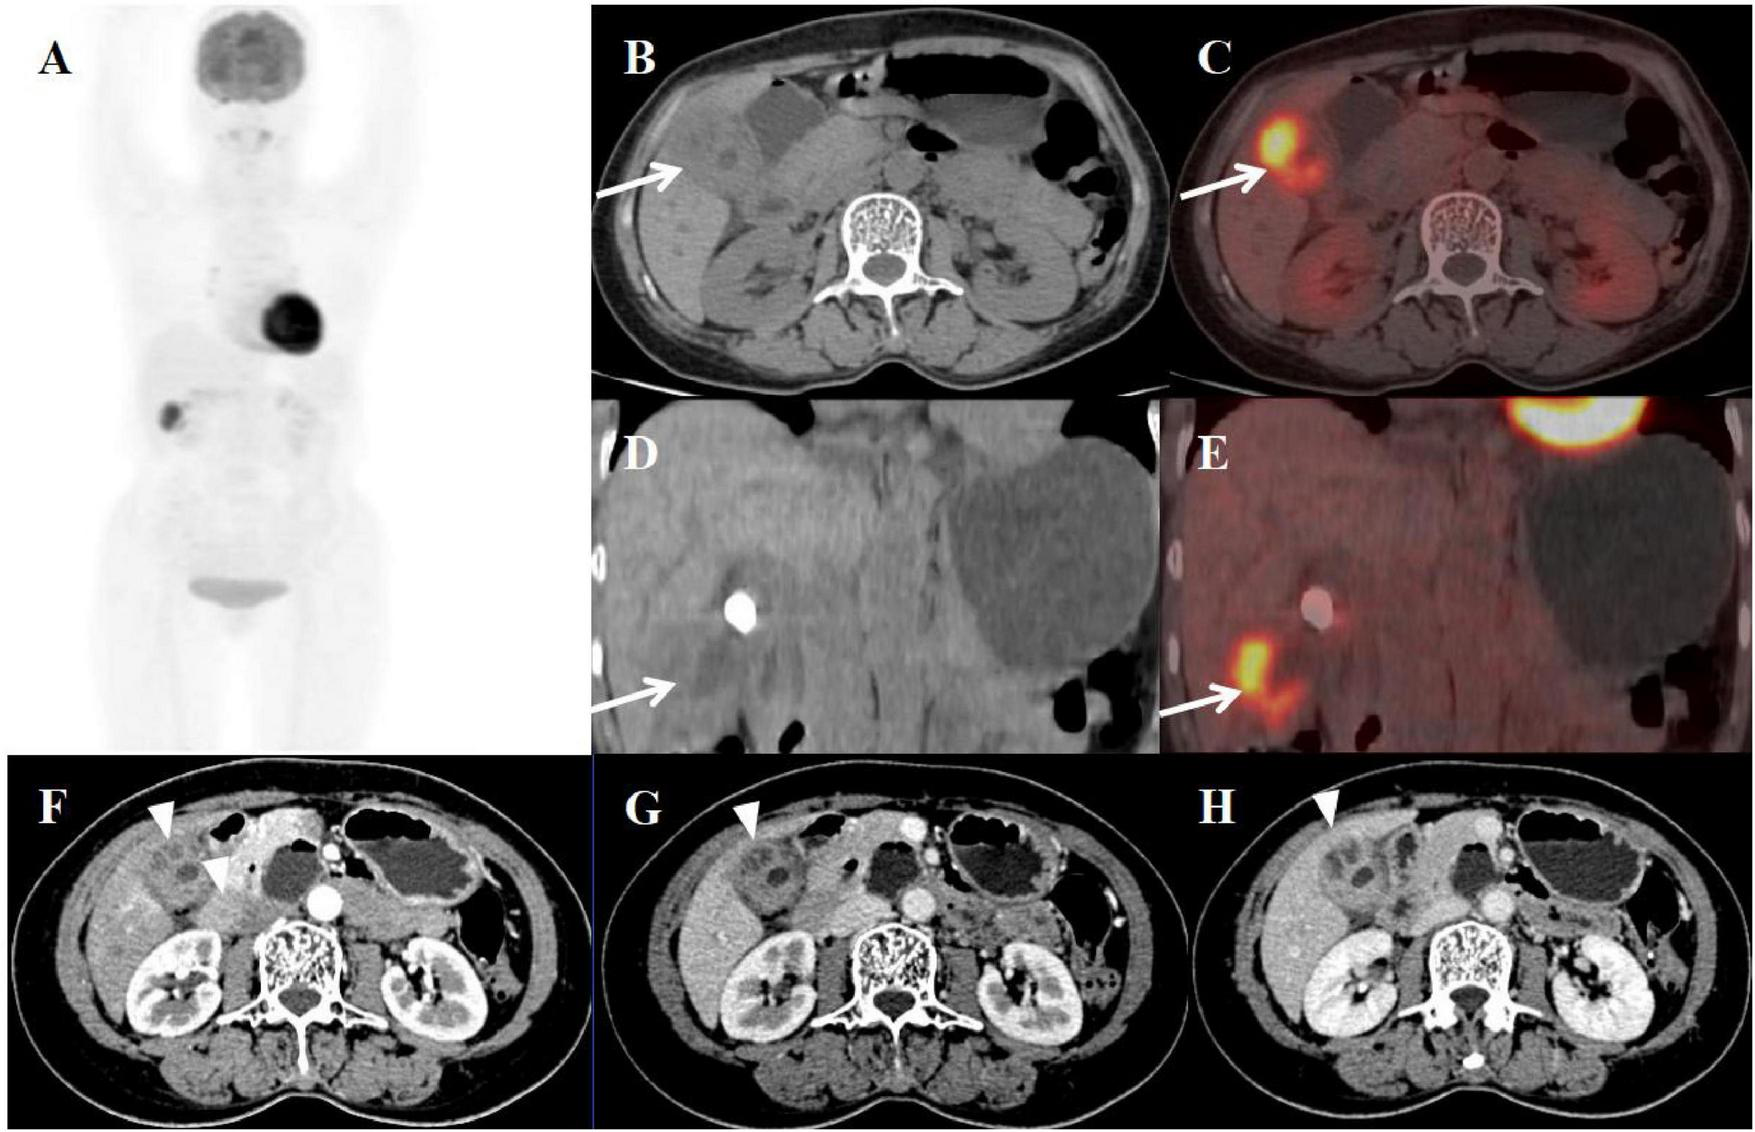

A 58-year-old woman presented with a three-month history of recurrent right upper abdominal pain and a five-year history of untreated gallbladder stones. Physical examination revealed a positive Murphy’s sign. Laboratory evaluation demonstrated elevated ferritin (355.90 ng/mL), increased C-reactive protein (CRP: 15.54 mg/L), and mildly elevated gamma-glutamyl transferase (49 U/L). All tumor markers were within normal limits. Contrast-enhanced CT demonstrated impacted gallbladder stones with focal wall thickening (maximally 20 mm at the fundus) showing heterogeneous density, progressive persistent enhancement, and internal septations – findings initially suspicious for gallbladder carcinoma with hepatic invasion. Subsequent PET/CT confirmed these features with additional findings of narrowed lumen, intramural hypodense nodules, and markedly increased FDG avidity (SUVmax 10.6), while maintaining mucosal continuity despite an indistinct hepatobiliary interface (Figure 3). The patient required conversion to open cholecystectomy with concomitant partial hepatectomy due to extensive inflammatory adhesions. Histopathological examination of the surgical specimen established the definitive diagnosis of xanthogranulomatous cholecystitis (XGC), demonstrating the characteristic histologic triad of: (1) foamy histiocytic aggregates, (2) chronic inflammatory infiltrates, and (3) fibroblastic proliferation with cholesterol clefts.

Figure 3. Female, 58 years old. (A) (whole body MIP), (B, C) (Axial CT and fused axial PET-CT), (D, E) (Coronal CT and fused coronal PET-CT), and (F–H) (axial, multiphasic contrast-enhanced CT). 18F-FDG PET/CT Imaging Findings: The gallbladder lumen was narrowed with impacted calculi (D). Focal thickening of the gallbladder wall was present, most prominent at the fundus (approximately 20 mm) (B, D, arrow ↑), accompanied by hypodense intramural nodules. There is markedly increased FDG avidity, with an SUVmax of 10.6 (C, E, arrow ↑). The hepatobiliary interface is indistinct, though the gallbladder mucosal line remains continuous, and no enlarged lymph nodes are visualized in the surrounding region. Multiphase contrast-enhanced CT reveals progressive delayed enhancement of the thickened gallbladder wall, with ring enhancement of the wall nodules observed in the delayed phase (H, arrow ▲) (CT values: 44 HU non-contrast, 67 HU arterial, 76 HU venous, 83 HU delayed).